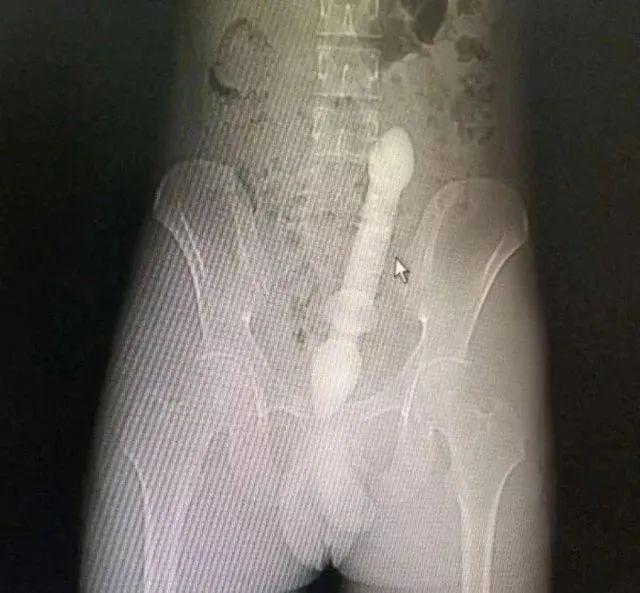

医生会通过一系列检查如直肠指诊、X 线来确定体内的异物是什么,在什么位置,这一点非常关键,因为只有搞清楚里面的真实情况,医生才能找到合适的方法把异物取出。